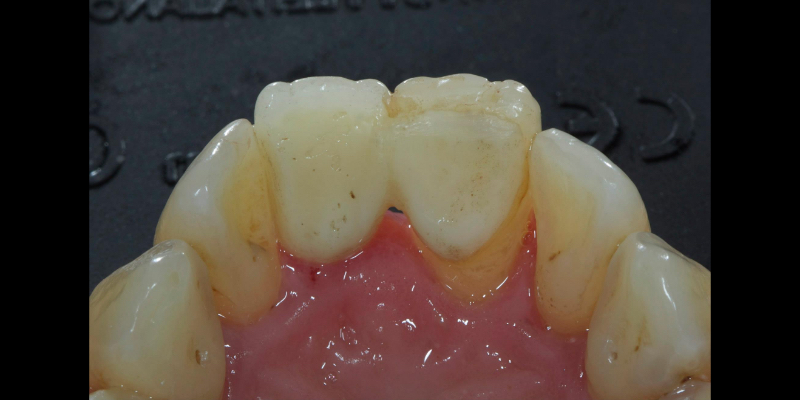

Take Arthur, a 76-year-old man who presented with a vertical root fracture of his upper left central incisor. His medical conditions precluded his request for an implant, so he agreed to the proposal for an adhesive bridge instead.

The tooth was extracted and for four months the pontic site was conditioned with a removable Essix-type of denture (Fig. 1).

An e.max (lithium disilicate), one-wing (adjacent central being the retainer) bridge was placed, which resulted in an acceptable outcome (Figs. 2-4) that was more timely and at a lower financial and biological cost to the patient than the implant Arthur initially thought he wanted.